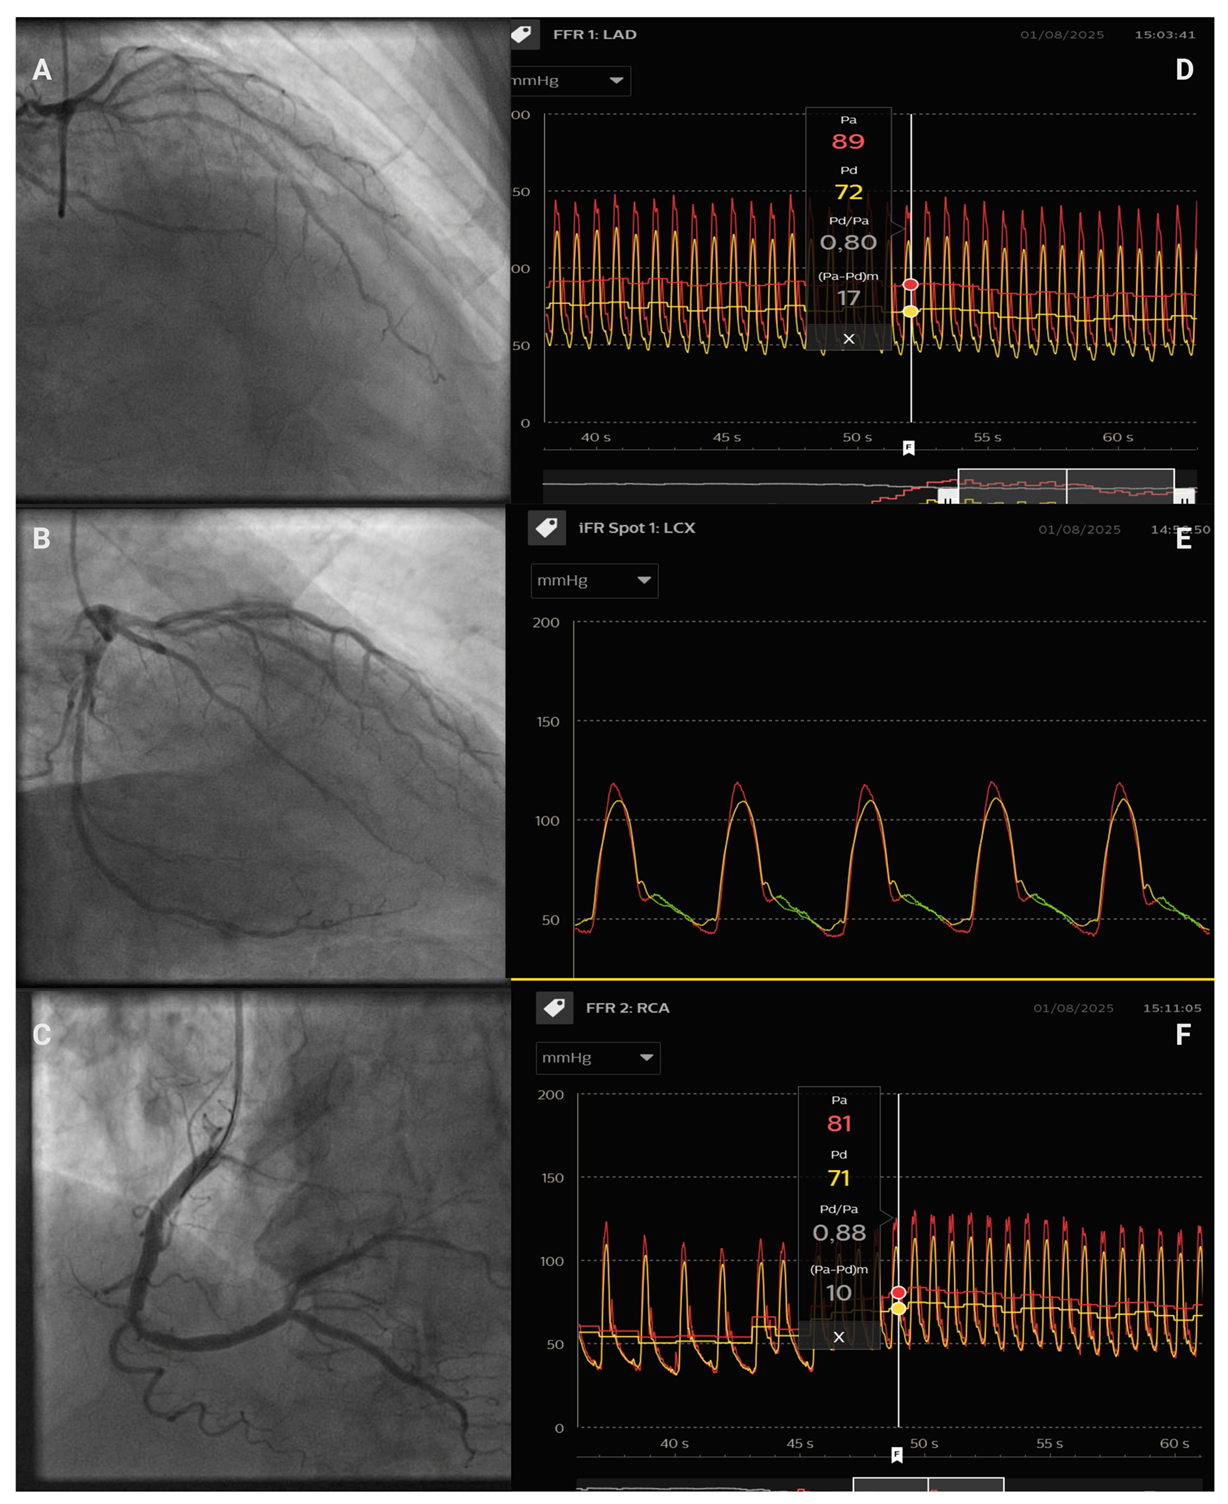

7.1. IVUS Versus FFR